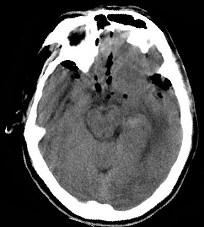

男,32岁,外伤后一天,CT检查如图,下面哪项诊断最恰当()A.脑膜瘤B.脑出血并颅内积气C.脑出血D.颅脑外伤E.颅内积气

问题 男,32岁,外伤后一天,CT检查如图,下面哪项诊断最恰当()

选项 A.脑膜瘤 B.脑出血并颅内积气 C.脑出血 D.颅脑外伤 E.颅内积气

答案 B